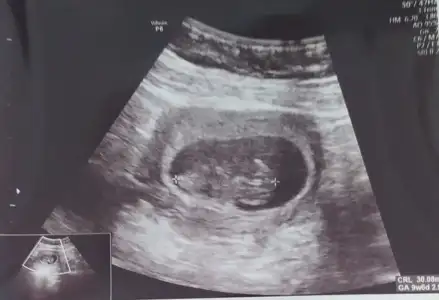

Tam değil kuzucum toplanmış dedi doktor 🤭 zaten bu doktordan pek bir şey anlayamıyorum açıkçası kendi doktorum ayrıntıyla gösteriyor buna gitme amacim kalbini duymak sağlıklı olduğunu görmekti gripten sonra nasıl diye bir baktık 😊 bak atayım hatta

Bu arada bebiş 10+0 çıktı normalde 9+3 tük. Yani sürekli değişiyor şimdilik bir tarih belirlemeyelim böyle olması çok normal ilk 3 ay dedi şimdi de Sat ı yakalamış miniğim.

12. Haftadan sonra hafta belirleriz dedi öyle bu sefer çok iyi yaklaştı sağolsun 🤗

Kafası nerede onu bile cozebilmis değilim 😂 10 gün önce kafa solda idi şimdi sağa dönmüş sanırım hiç anlamıyorum 🤷‍♀️